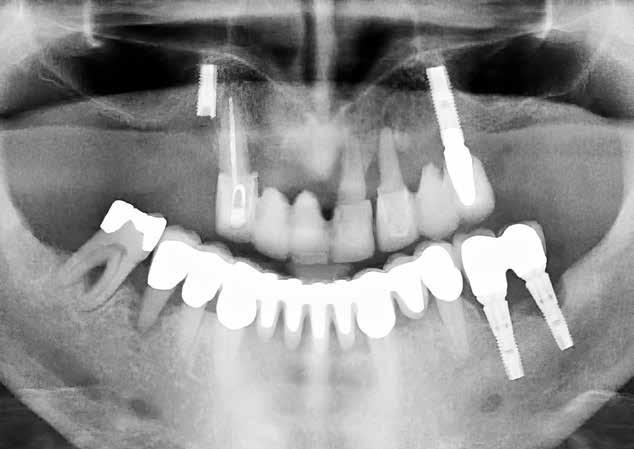

Immediat

implantat:

” Vi udnytter biologien til at få et bedre resultat”

Når implantatet bliver sat op umiddelbart efter ekstraktionen, kan det væv, der var omkring den fjernede tand, skabe gode betingelser for, at implantatet sidder fast, og at det endelige resultat af restaureringen ender godt.

Tanden kan ikke reddes og må trækkes ud. Implantatet sættes i, og en midlertidig tand monteres - alt sammen i én behandlingsseance. Patienten går ind ad døren med en ødelagt fortand og kan gå ud igen med et smil, der både ser naturligt ud og er funktionelt.

Sådan fungerer et immediat implantat. Behandlingsmetoden, der både bevarer tandens væv bedre og reducerer patienternes behandlingstid, foregår i et tæt parløb mellem kæbekirurgien og protetikken. Netop sådan et parløb har specialtandlæge i tand-, mund- og kæbekirurgi, Kristian Thesbjerg, og tandlæge med ekspertise i protetik, Morten Tang Jensen, haft siden 2017.

- Jeg var på det tidspunkt på et kursus i Spanien, hvor jeg blev præsenteret for immediat implantatmetoden, og jeg blev ret begejstret. Da jeg kom hjem, kontaktede jeg Morten og sagde: Det skal vi da prøve, fortæller Kristian Thesbjerg.

Siden har de to tandlæger arbejdet med metoden og gradvist udviklet og

forfinet den til, hvad den er i dag, hvor den både giver flotte resultater og en stor tilfredshed hos patienterne.

Bedre betingelser for implantatet Metodens styrke ligger i, at man udnytter biologien til at give bedre betingelser for implantatet. Morten Tang Jensen forklarer:

- Når vi indsætter implantatet hurtigt, efter at tanden er trukket ud, tilpasser vævet sig nemmere, end hvis vi venter, og det klapper sammen. Man kan sammenligne det med en arm i gips, som jo hurtigt bliver tynd og mister muskelkraft. Det samme sker i mundhulen.

Grundig klinisk undersøgelse Ikke alle er kandidater til immediat implantat. Akkurat som det gælder

alle typer af implantatbehandlinger, er det nødvendigt at se på den generelle sundhed hos patienten.

- Har du fx tre andre knækkede tænder og er ryger, er du ikke velegnet til lige netop denne type af implantatbehandling, siger Morten Tang Jensen.

I samme ombæring pointerer Kristian Thesbjerg, at behandlingen kræver en grundig klinisk undersøgelse af patienten med røntgenbilleder og CBCT-scanninger af munden for at vurdere egnetheden til en immediatbehandling.

- Man skal heller ikke gå i gang, før man er sikker på at have et sted at forankre implantatet, og så kræver teknikken både kirurgisk præcision og en protetik, der er grundigt planlagt, siger han.